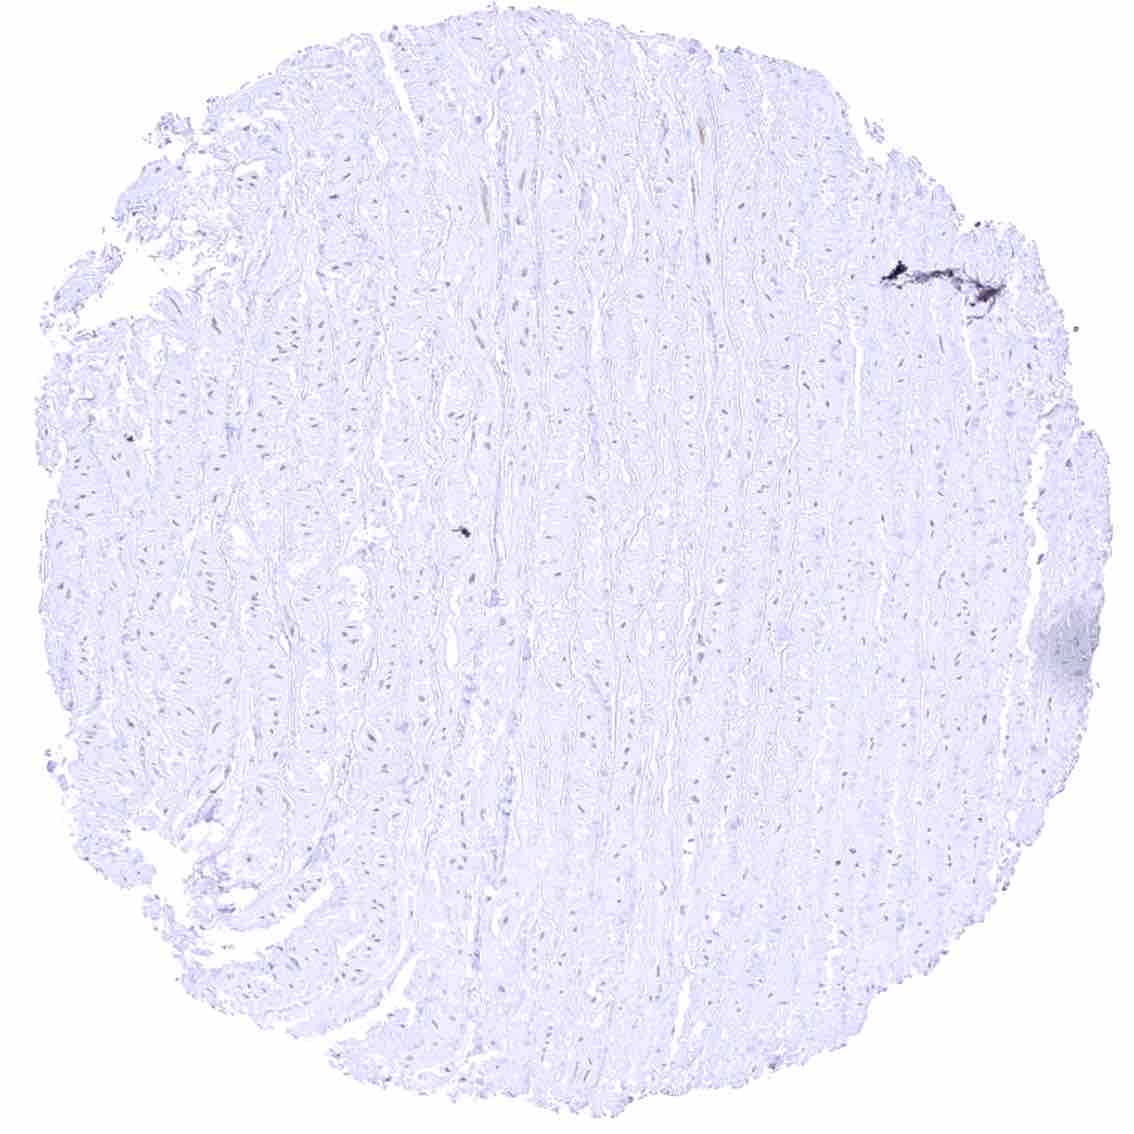

Aorta, media